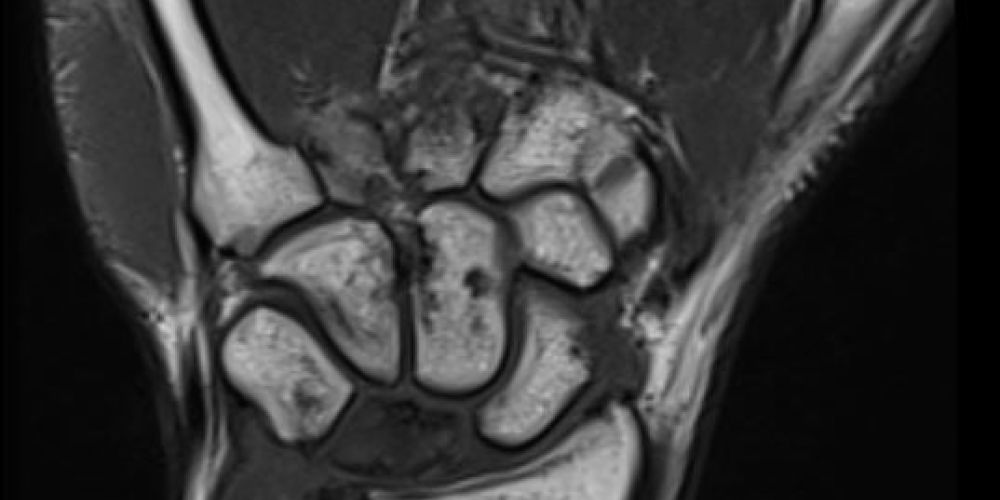

ToggleHastalığın gelişimi genellikle yavaş ilerler ve genellikle 20-40 yaşları arasındaki bireylerde görülür. Çoğunlukla tek bir elde görülse de, nadiren her iki elde de Kienböck hastalığı aynı anda gelişebilir. Erken dönemde hastalığın teşhisi zor olabilir, çünkü radyolojik bulgular henüz belirginleşmemiştir. Ancak hastalığın ilerleyen evrelerinde lunat kemiğinde şekil bozuklukları, çökme, sklerozlu alanlar ve kemik parçalanmaları görülebilir. Bu süreçte hastalar, özellikle bilek hareket ettirilirken ağrı ve zayıflık hissederler. El bileğinde kısıtlı hareket, özellikle bileğin yukarıya kaldırılmasıyla ağrının artması, hastalığın karakteristik belirtilerindendir. Erken teşhis için manyetik rezonans görüntüleme (MRG) önemli bir rol oynar ve bu yöntem, hastalığın başlangıcını belirlemede yüksek hassasiyete sahiptir. Ayrıca, ileri evrelerde bilgisayarlı tomografi (BT) görüntülemesi de kullanılabilir.

İlk evrede, X-ray (röntgen) görüntüleri normaldir, ancak MRI ile lunat kemiğinde düşük sinyal görülür. Bu, lunat kemikte henüz belirgin bir morfolojik değişiklik olmadığını, ancak kan dolaşımının ve beslenmenin bozulduğunu gösterir. Bu dönemde hastalığın erken teşhisi zor olabilir.